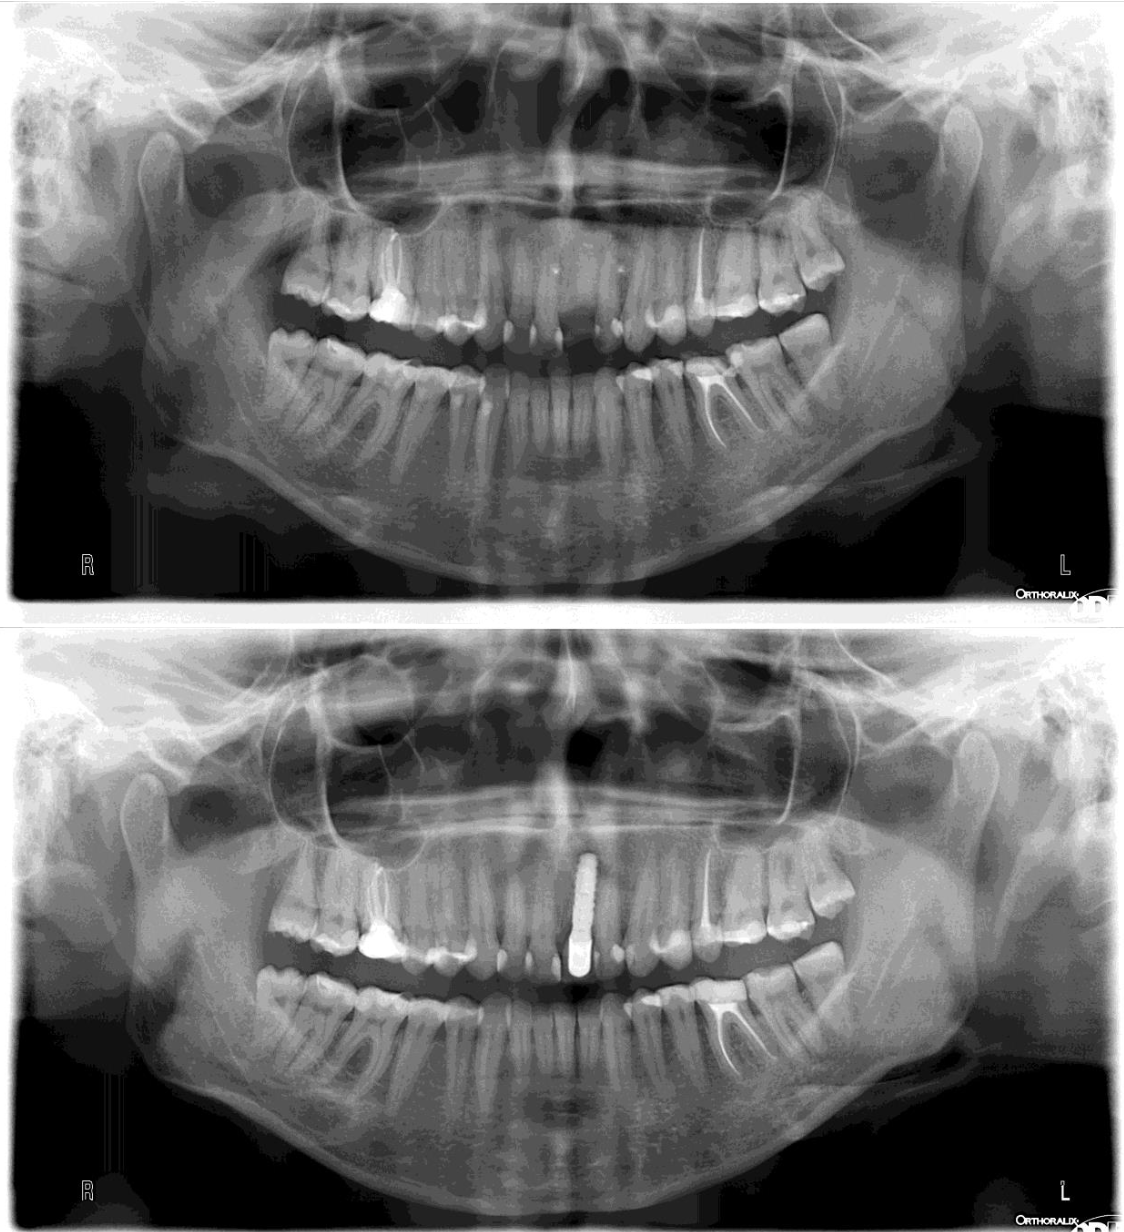

Implanty zębowe (implanty dentystyczne) to innymi słowy zamienniki korzenia zębowego, które umiejscawiane są w kości żuchwy bądź szczęki. Ich osadzenie pozwala stworzyć koronę, most lub protezę, która pozwoli uzupełnić braki w uzębieniu. Implanty zębowe to opcja, dzięki której nie maskujemy niedoskonałości, a uzupełniamy uśmiech w prawidłowo funkcjonujący oraz prezentujący się naturalnie nowy ząb. Wykonanie z biozgodnego tytanu sprawia, że organizm doskonale go przyjmuje, a prawidłowo chirurgicznie wszczepiony implant zostaje obudowany przez kość (tzw. osteointegracja), dzięki czemu ząb jest stabilny i mocno osadzony.

Sam implant na tym etapie nie uzupełnia braku w uzębieniu. Pełna funkcjonalność zapewniona jest dopiero po zamocowaniu w implancie korony, mostu lub protezy. W części protetycznej uzupełniania uśmiechu – wykonywanej po pełnym procesie osteointegracji – możliwe jest założenie nowego zęba lub zębów.